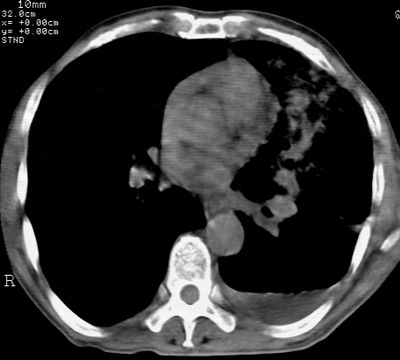

左肺门肿块,相应支气管闭塞,左肺上叶、舌叶大片及散在高密度影,部分呈不张改变,两肺纹粗乱,左侧胸腔积液。考虑左侧中央型肺癌伴阻塞性改变。

左肺门见巨大软组织肿块影,直径约--,境界清,左上肺叶支气管变窄,左上肺舌叶见大片状密实影,余肺纹理增多、紊乱、纤细、部分网格状,两肺透亮度增高,纵隔内见增大多发淋巴结影,心影略左偏,左侧少量胸腔积液。

左侧中央型肺癌伴左上肺舌叶不张、纵隔淋巴结转移,左侧少量胸腔积液。